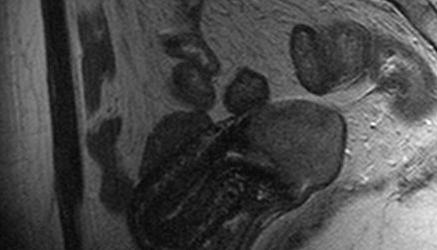

"Hace una semana hicimos un procedimiento llamado laparoscopía para identificar el sitio donde íbamos a implantar el tejido, y el día de hoy hicimos el trasplante con éxito", señaló.

Precisó que se trató de un trasplante autólogo, es decir de la misma paciente, y ortópico, en que el tejido se implantó donde antes estaban los ovarios, pues existe la posibilidad de implantarlo en otros sitios, pero con pocas probabilidades restaurar la función reproductiva.